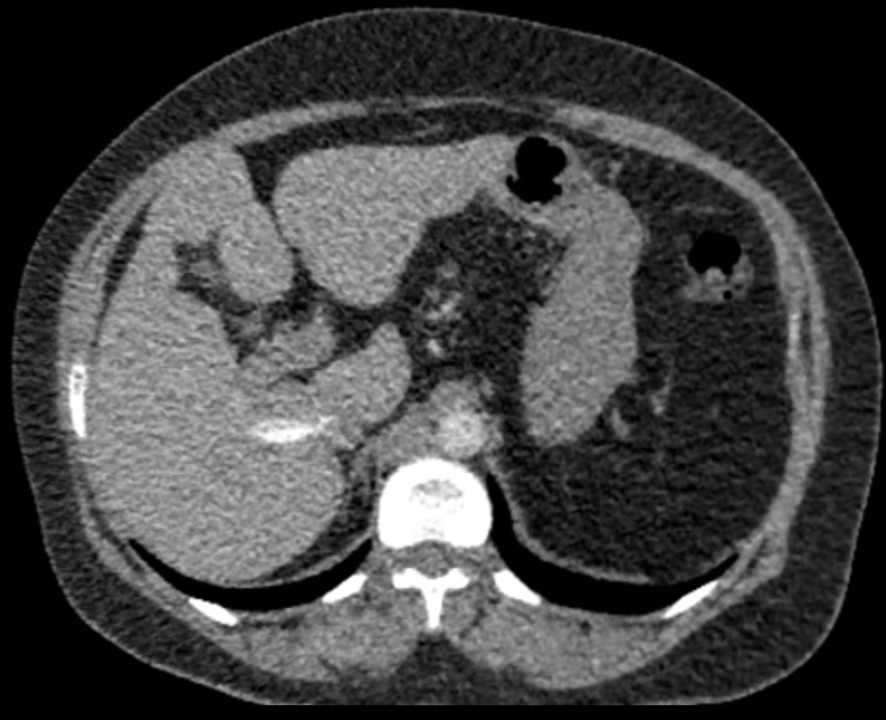

Clinical Case [Uncaptioned image] [Uncaptioned image]

Image Findings: The patient underwent contrast-enhanced computed tomography which showed features of a congested liver with flip-flop pattern of enhancement. Hepatic veins show hypoattenuation on delayed phase. An accessory hepatic vein is also noted in segment VI. A diagnosis of Budd Chiari syndrome (BCS) was made on the basis of the clinical and imaging features. The patient was referred to the interventional radiology team for an endovascular rescue. On conventional venogram, the diagnosis of BCS was confirmed as the hepatic veins were thrombosed. An accessory segment VI hepatic vein was noted draining into the IVC…

Title: Accessory right inferior hepatic vein [Uncaptioned image] [Uncaptioned image]

Discussion:Marked dilatation of the pulmonary trunk (6.7 cm) with the right (5.4 cm) and left (4 cm) main branches. Lung window shows mild bilateral diffuse faint groundglass centrilobular lung nodules that may reflect an underlying infection. Scans through the upper abdomen revealed average size cirrhotic liver and reflux of contrast into the IVC and hepatic veins with Incidental opacification of accessory right inferior hepatic vein…